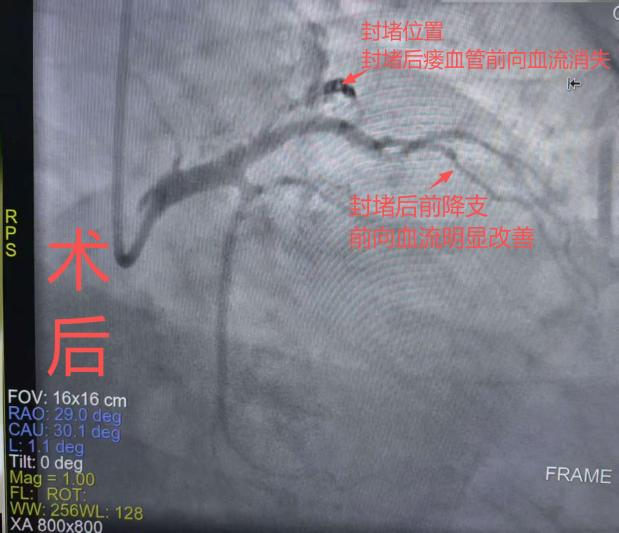

在过去,这类疾病的治疗主要依赖外科开胸手术,不仅创伤大、出血多,还面临较高的术后并发症风险,对患者身体耐受度要求高,恢复周期也更长。而此次我院采用的介入封堵技术,彻底打破了这一局限——通过微创方式经血管穿刺,将弹簧圈精准输送至瘘管部位完成封堵,全程无需开胸,最大限度降低了手术对患者的身体损伤。

术后,患者恢复情况良好,异常血流问题得到彻底解决,充分体现了微创介入治疗在心脏畸形矫正中的显著优势。